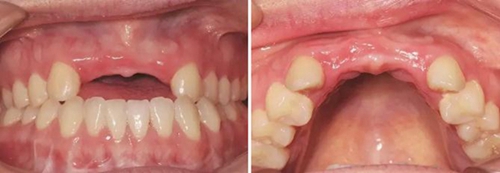

圖1 植骨術(shù)前口內(nèi)正面觀 圖2 植骨術(shù)前口內(nèi)頜面觀

患者,女性,23歲,大學(xué)生?;颊哂?年前因外傷導(dǎo)致上前牙缺失,期間行可摘局部義齒修復(fù),自覺每天摘帶不便,且影響正常發(fā)音及美觀,至我科要求種植修復(fù)。平素體健,無全身系統(tǒng)性疾病,無特殊藥物服用史,無藥物、材料等過敏史,無吸煙、夜磨牙等不良習(xí)慣??谕鈾z查見口腔頜面部對(duì)稱,張口度正常,中位唇線,中位笑線??趦?nèi)檢查見12、11、21、22缺失,缺牙區(qū)牙槽嵴薄。覆牙合覆蓋淺,23反牙合??谇恍l(wèi)生狀況良好。拍攝CBCT示:12位點(diǎn)可用牙槽骨高度為16.4mm,寬度為3.6mm;22位點(diǎn)可用牙槽骨高度為19.5mm,寬度為3.2mm。

(1)2014年1月:初診明確診斷為12、11、21、22缺失,缺牙區(qū)牙槽嵴較薄,拍攝CBCT(kavo卡瓦,德國)顯示:缺牙區(qū)存在水平向骨缺損,12位點(diǎn)可用牙槽骨高度為16.4mm,寬度為3.6mm;22位點(diǎn)可用牙槽骨高度為19.5mm,寬度為3.2mm,唇側(cè)骨板稍有凹陷,明確治療計(jì)劃。